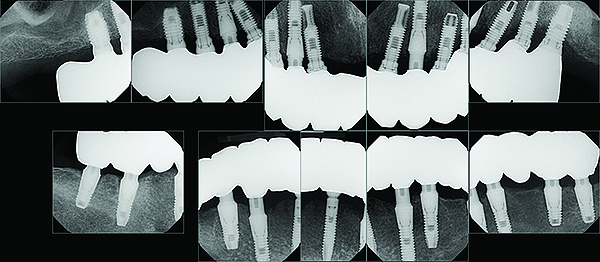

The maxillary prototype was adjusted, polished, and left to function with the mandibular provisional. The definitive maxillary zirconia restoration was then completed from the information provided by the prototype, and the cutbacks for the facial porcelain (Nos. 6 through 11) were done after milling but before sintering. Subsequently, the mandibular prototype was adjusted to the sintered and colored maxillary zirconia framework before the application of porcelain to Nos. 6 through 11 and final glazing (Figure 11). Following this step, the mandibular definitive monolithic zirconia restoration was milled, colored, and sintered. The facial porcelain (Nos. 6 through 11) was applied, and then both maxillary and mandibular restorations were stained and glazed (Figure 12). Both bridges were inserted at the same time (Figure 13 through Figure 15). Minor occlusal adjustments and oral hygiene access was verified and the zirconia surfaces polished. The bridge screws were torqued to 20 Ncm according to the manufacturer’s recommendation, and No. 24 was luted with a provisional cement. Postoperative radiographs were taken (Figure 16).

Fig 16. Post-treatment full-mouth radiographs.

Figure 16